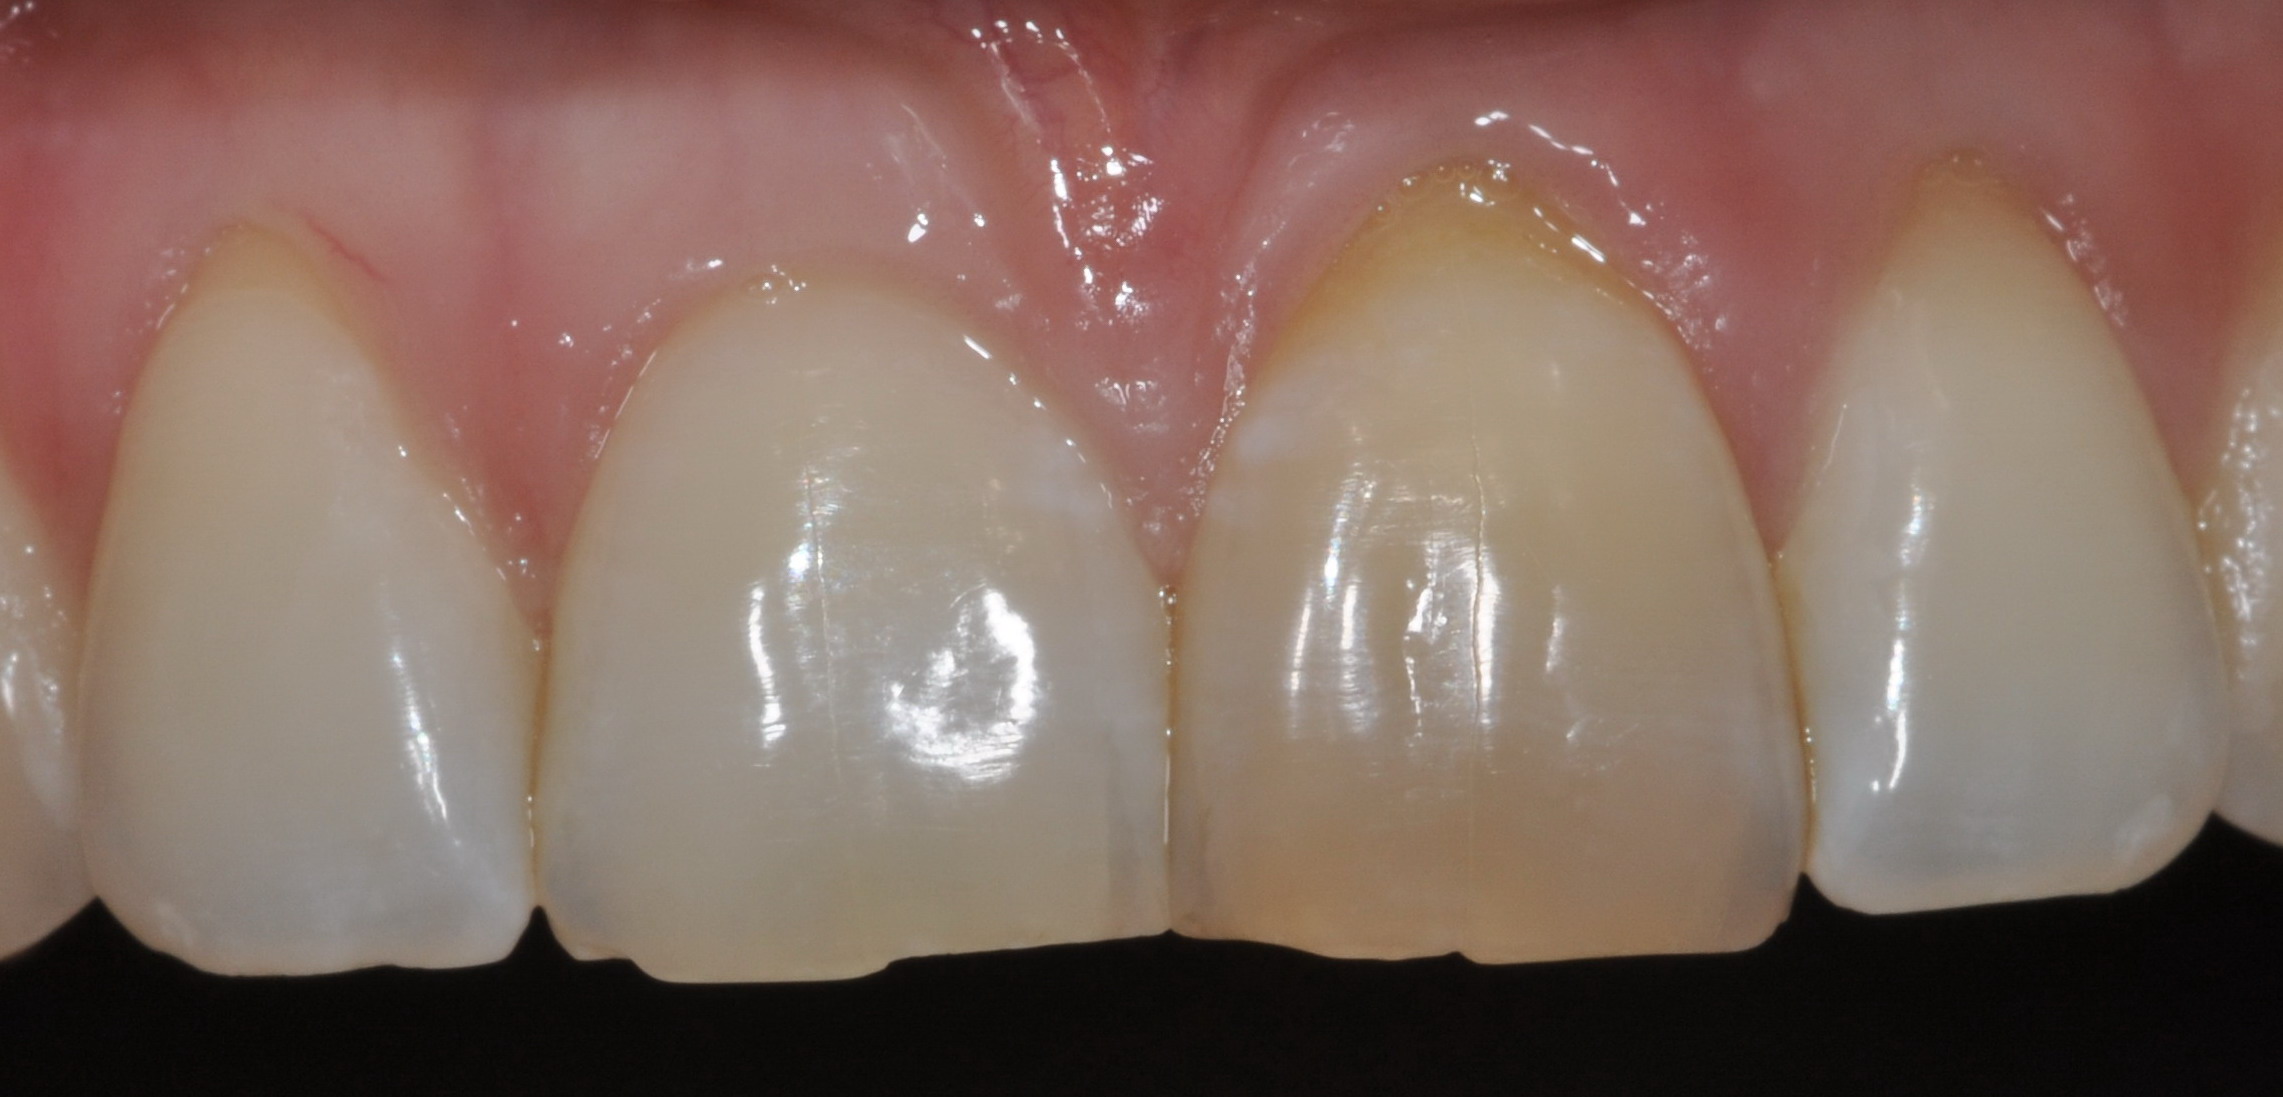

Dopo

Dente 2.1 dopo aver effettuato lo sbiancamento interno